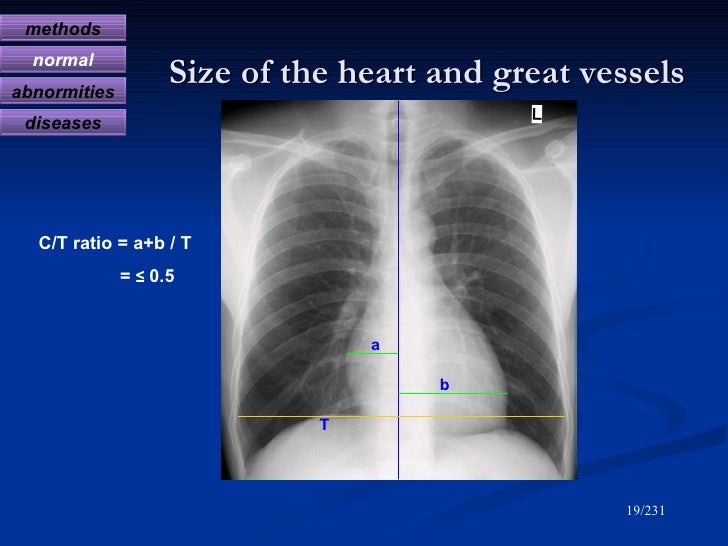

Diagnostic radiology of cardiovascular 2009 Diagnostic Radiology Chest And Cardiovascular Imaging this new edition is a complete guide to diagnostic imaging of the chest and cardiovascular system. radiography allows visualization and assessment of the chest wall, mediastinum, and hila including the heart and great vessels, central airways,. cardiovascular imaging is a branch of diagnostic radiology where a cardiac radiologist oversees or performs medical. Diagnostic Radiology Chest And Cardiovascular Imaging.

Diagnostic radiology of cardiovascular 2009 Diagnostic Radiology Chest And Cardiovascular Imaging this new edition is a complete guide to diagnostic imaging of the chest and cardiovascular system. cardiovascular imaging is a branch of diagnostic radiology where a cardiac radiologist oversees or performs medical. radiography allows visualization and assessment of the chest wall, mediastinum, and hila including the heart and great vessels, central airways,. Diagnostic Radiology Chest And Cardiovascular Imaging.